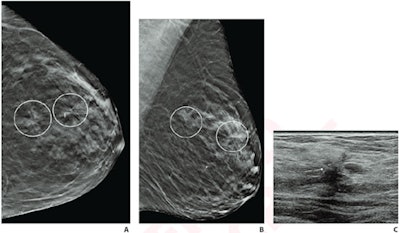

(A) Craniocaudal and (B) mediolateral oblique DBT images show two areas of architectural distortion in upper outer left breast (circles) that persisted on additional diagnostic tomosynthesis images (not shown). (C) Transverse grayscale ultrasound image of upper outer breast shows irregular hypoechoic mass with associated architectural distortion at 12:30 (arrow), corresponding to posterior architectural distortion. No ultrasound correlate was identified for anterior architectural distortion. Ultrasound-guided biopsy of posterior distortion revealed malignancy (invasive lobular carcinoma). Tomosynthesis-guided biopsy of anterior distortion yielded benign pathology (stromal fibrosis).The study authors looked at retrospective data for 402 women collected between 2017 and 2019. Out of the total, 372 women had single architectural distortion (145 benign, 121 high risk, 105 malignant, 1 other), and 30 women had multiple visualized distortion. From these two groups, 66 women had biopsied architectural distortion (10 benign, 35 high risk, 21 malignant).